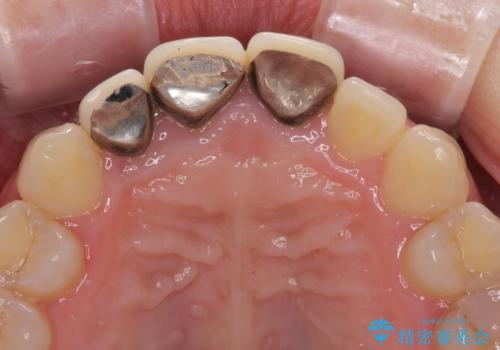

- 以前に装着した前歯のクラウンの縁が見えていることを気にして来院された患者様です。

根尖部に病変のある2歯は事前に根管治療を行い、オールセラミッククラウンにて補綴することとしました。